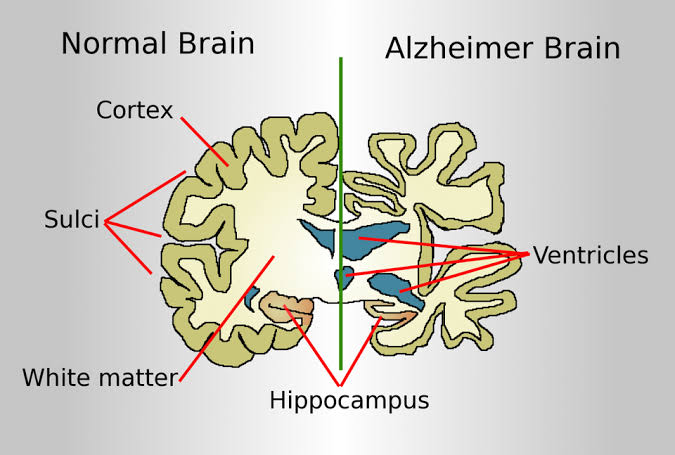

The cause of Alzheimer disease is unknown. Scientists know that in Alzheimer disease there is large build-up of proteins called amyloid within brain cells. These proteins occur normally, but not yet understand why they build up in large amounts. The disease process can go on for many years without symptoms, but as more and more proteins form brain cells,the cells lose their ability to function and eventually die. This causes the affected parts of the brain to shrink.